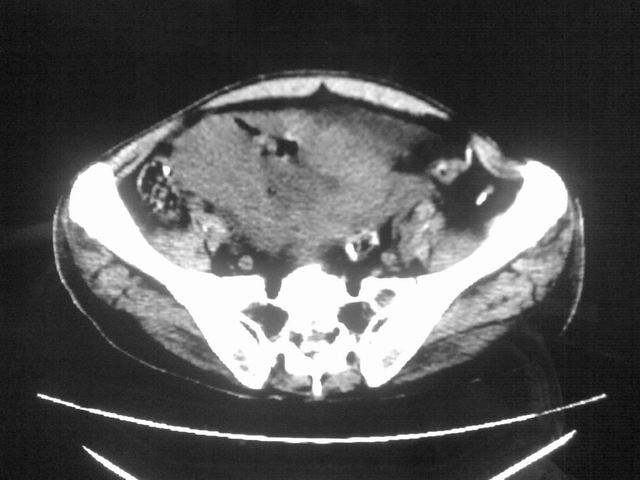

患者m 56岁,盆腔及下腹部胀痛半年,加重1月余,消瘦\中重度贫血.(附:平扫时直肠的高信号为,残留的钡剂).补一下病史:胃镜及纤维结肠镜均无明显异常.

首先是病灶的定位,平扫看很象肠管肿瘤但既然纤维结肠镜正常就可以除外结肠病变,增强成不均匀强化,位于右下腹部应该首先考虑回肠末段占位性病变,1淋巴瘤,2间质瘤,3腹膜后神经原肿瘤待除外,

首先是病灶的定位,平扫看很象肠管肿瘤但既然纤维结肠镜正常就可以除外结肠病变,增强成不均匀强化,位于右下腹部应该首先考虑回肠末段占位性病变,以间质瘤或淋巴瘤可能性大.,

膀胱及直肠间有不规侧的软组织密度影,内密度不均匀。其内有坏死囊变,前列腺及精囊腺,膀胱后壁受浸。结合病史考虑腹膜后肉瘤可能性大。